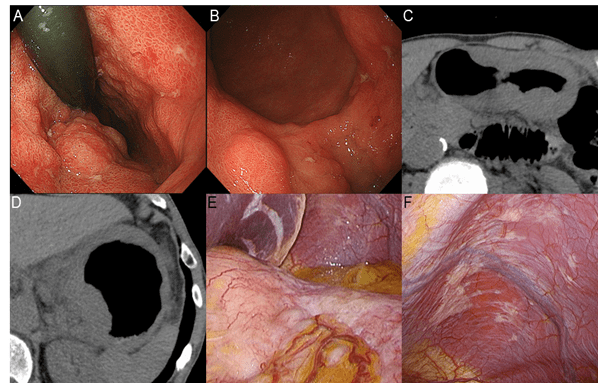

At 45 months after the initial diagnosis, the patient complained anorexia and developed 5 kg weight loss. He finally requested surgical resection. Endoscopically, lesion 1 involved lesion 2 and had formed giant folds (Figures 3A, B). Abdominal Computed Tomography (CT) showed circumferential wall thickening from the esophagus to the lower part of the body and enlarged lesser curvature lymph nodes (Figures 3C, D). Staging laparoscopy revealed that the tumor was extensively exposed on the serosa, mainly located in the cardia, and the lesser omentum was thickened by Peritoneal Metastasis (PM) (Figure 3E). Disseminated nodules were also found on the left diaphragmatic surface and rectovesical fossa (Figure 3F). Peritoneal lavage cytology was positive for cancer cells. The postoperative diagnosis was unresectable AGC, cT4aN+M1P1, and cStage IVB. He agreed to undergo systemic chemotherapy.

Figure 3: Clinical findings 45 months after the initial diagnosis when the patient requested surgical resection, complaining of anorexia and weight loss. Endoscopically, lesion 1 involved lesion 2, forming giant folds (A,B). Abdominal CT showed circumferential wall thickening from the esophagus to the lower part of the gastric body and enlarged lesser curvature lymph nodes (C, D). Staging laparoscopy revealed that the tumor was extensively exposed on the serosa, mainly located in the cardia, and the lesser omentum was thickened by peritoneal dissemination (E). Disseminated nodules were also found on the left diaphragmatic surface (F).